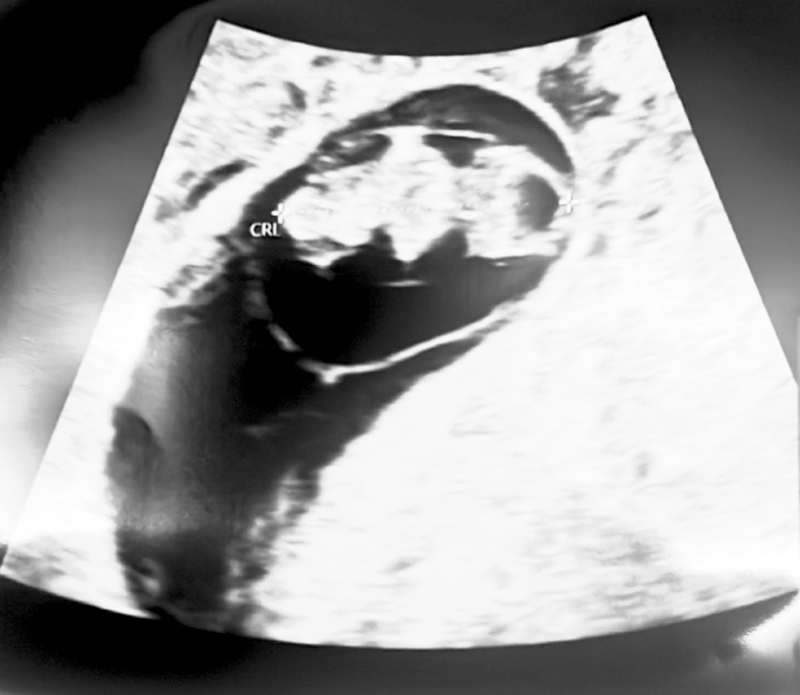

心拍も無事確認できて母子手帳もGOが出たのですが、胎嚢の周りに黒い影がいくつかあるのが気になる、と先生に言われました。

添付をしてくださったエコーのお写真を拝見いたしました。

赤ちゃんの姿が写っている上の方に小さくいくつか写っているもののことになるのではと思いました。

実際にこれまでの経過から小さくなっていたりするようでしたら、今後吸収をされていくこともあるかもしれません。